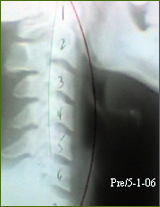

Phillip N. Had a reversed curve in his neck causing mid back pain, especially while working. After a few adjustments his pain disappeared and post exam revealed 92% correction of the neck curve.

“I consulted Dr. Capoferri after being referred to him by another doctor. My back pain made it difficult to work and sleep. My pain is now gone and my neck curve is corrected.”